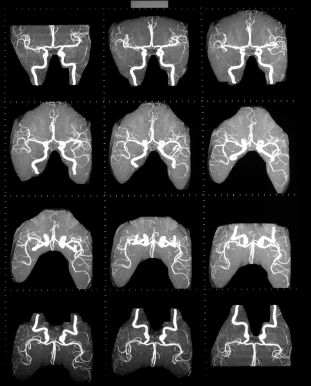

Диагностические процедуры для рентгеновских артерий. Краска вводится в артерию с помощью катетера или трубочку, которая позволяет сосудистых структур для визуализации.